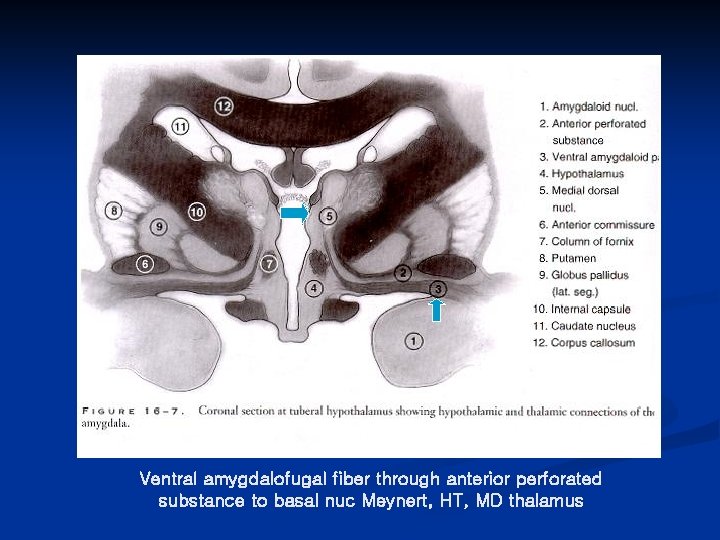

Anatomy of anterior thalamic nucleus n Blood supply Tuberothalamic (Polar) artery form P-com n Afferent *Mammillary body (mammillothalamic tract) *Ventral amygdalofugal fiber (inferior thalamic peduncle) n Efferent cingulate gyrus

Ventral amygdalofugal fiber through anterior perforated substance to basal nuc Meynert, HT, MD thalamus